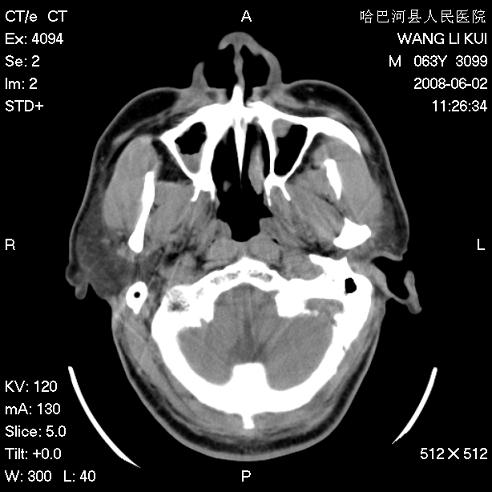

标题: CT13803:反复性鼻塞、流涕一年余 [打印本页]

标题: CT13803:反复性鼻塞、流涕一年余

副鼻窦炎,右上额窦积脓。左眼肌锥内见致密影,视神經受压

1.全组副鼻窦炎2.双侧上颌窦积液

1)全副鼻窦炎(左侧上颌窦黏膜下囊肿或息肉)。2)左眼眶肌锥内不规则小结节状软组织密度影;考虑为小血管瘤可能。建议行ct增强扫描检查。

全组副鼻窦炎,左侧肌锥内不规则形软组织肿块影,与眼外肌密度相当,左侧视神经受压,肿块与视神经及眼外肌分界清晰,眼外肌无增粗,眶壁无破坏,球后脂肪间隙不模糊,考虑良性改变,小血管瘤或神经源性肿瘤可能,建议增强扫描。

谢谢,增强扫描做了,眶内病灶与海绵窦同步明显强化,血管瘤